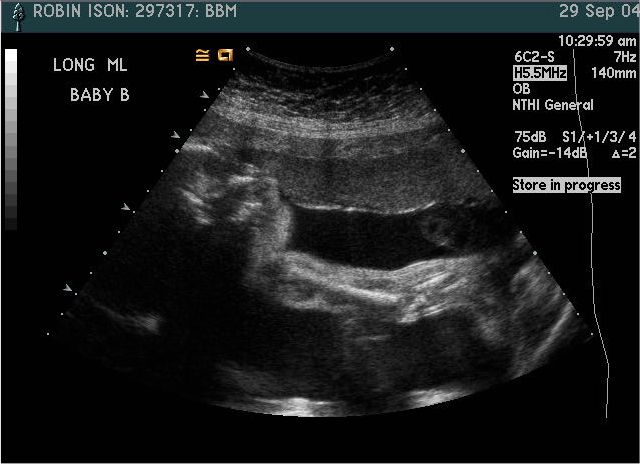

Baby B

Pictures from Ultrasound at 26 weeks.